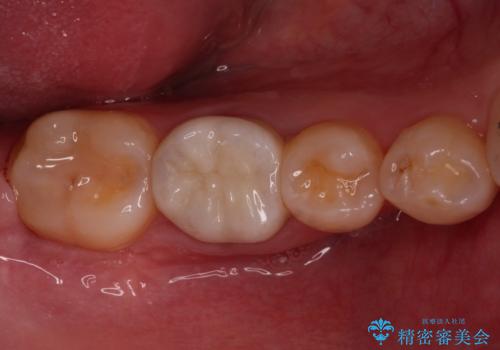

矯正治療を行う前に、根管治療の必要な上顎前歯と下顎大臼歯の根管治療を行い、矯正治療の途中で下顎の欠損部にインプラント埋入することとし、矯正治療後に補綴治療を行うこととしました。

矯正治療中にインプラント埋入を行うなど、余計な時間や無駄のない治療を行うことができました。